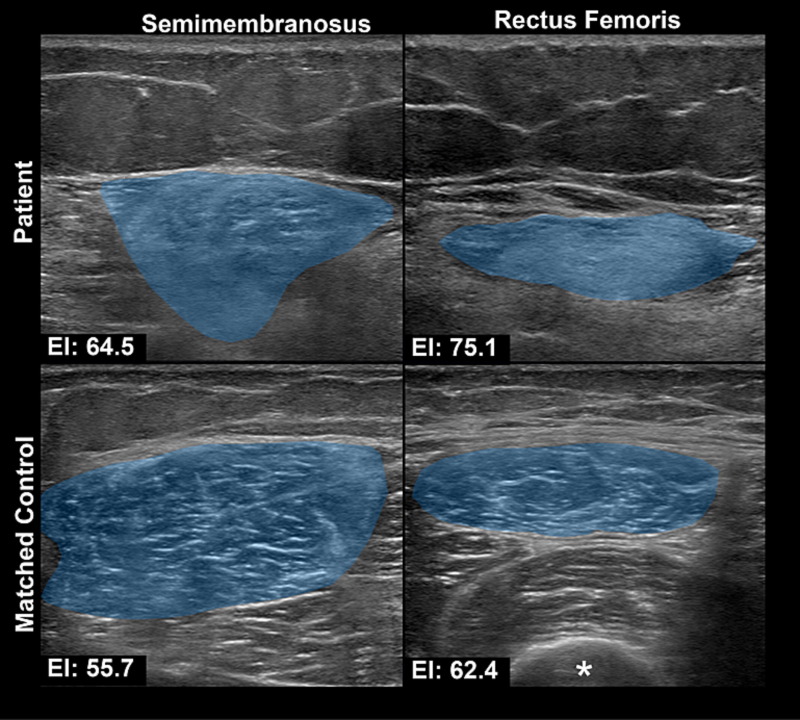

This is a 60-year-old woman with a history of ischemic stroke 5 years ago, previously presenting with aphasia and right-sided weakness, with complete recovery. She now presents with recurrent aphasia and right-sided weakness. In the ED, she was found to have a urinary tract infection with sepsis. MRI brain DWI showed no new diffusion restriction. After 2 days of antibiotics, her neurological deficits completely resolved. Question: What do you see on the MRI? How do you explain her recurrent aphasia and right-sided deficits despite no new imaging changes? #Neuroradiology #Neurology #Stroke #UTI #FOAMed